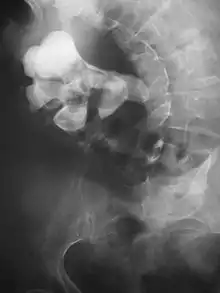

وفي حالة عدم توفر التصوير المقطعي المحوسب، يمكن إجراء فحص الحويضة الوريدية للمساعدة على تأكيد تشخيص التحصي البولي. وذلك عن طريق حقن مادة تباين في الوريد، ثم تصوير الكلى، والحالب، والمثانة. ويتم تحديد الحصوات الموجودة في الكلى، أو الحالب، أو المثانة بشكل أفضل من خلال استخدام عامل التباين. ويمكن أيضًا الكشف عن الحصوات عن طريق تصوير الحويضة من الوراء، حيث يتم حقن عامل تباين مماثل مباشرة في الفوهة البعيدة للحالب (حيث ينتهي الحالب عند دخوله المثانة).[46]